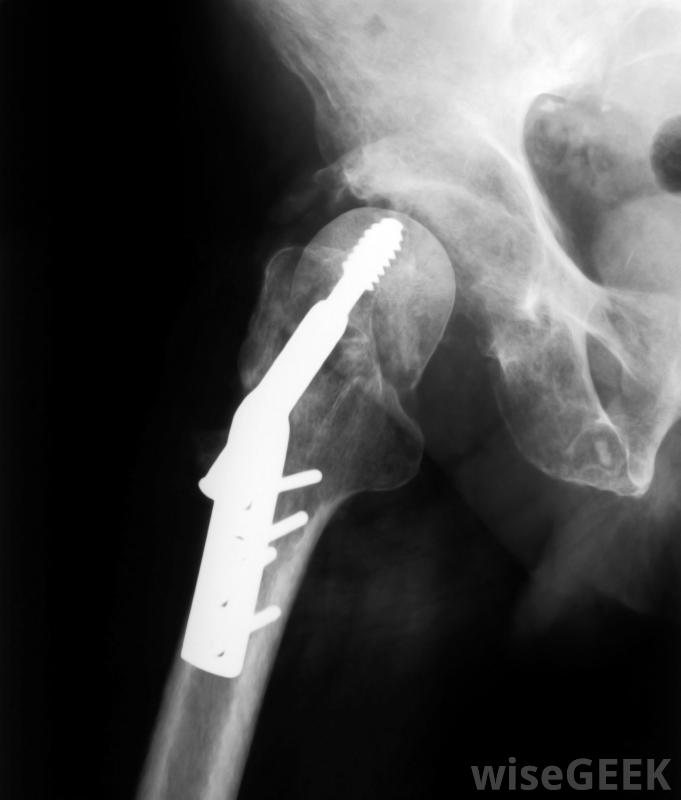

手術期間,動態髖關節螺釘被插入股骨。它由一個大螺釘組成,該螺釘以一定角度固定在股骨頭上,并與金屬板相連,它沿著股骨軸垂直定位,并用較小的螺釘固定到位。外科醫生使用X射線圖像確保髖部螺釘的精確定位。

在DHS手術期間,外科醫生在骨折處放置一個大金屬螺釘,并使用鋼板和一些較小的螺釘將骨頭固定在一起。